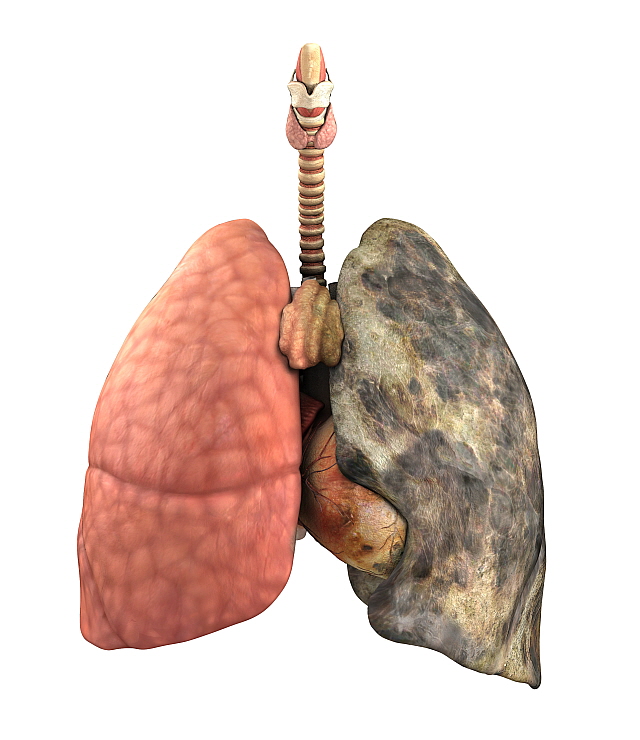

그렇다면 폐암 원인은 무엇일까요? 폐암의 가장 큰 발병 요인은 흡연입니다. 흡연자는 비 흡연자에 비해 폐암 발병확률이 15배~80배가량 높습니다.

폐암을 예방하는 방법은 금연 이외에는 확실히 밝혀진 것이 없다고 합니다. 폐암의 90%는 금연으로 예방이 가능하다고 합니다.

담배를 끊은 이후에도 폐암 발병 위험의 감소 속도가 느리기 때문에 원래 담배를 안 피우던 사람보다 폐암 위험도가 20년 앞선다고 합니다.